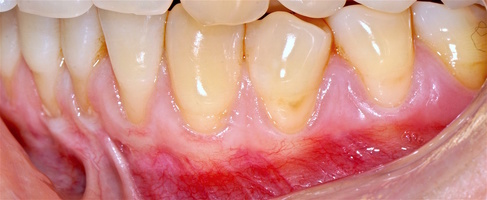

1. Генерализованные рецессии в области нижней челюсти оперировались в один этап все 12 зубов, фронтальный участок с аутотрансплантатом от 3.2 до 4.2 зубов. А дистальные участки от 3.6 до 3.3 и от 4.6 до 4.3 зубов с использованием пластического материала ТМО (dura mater) (рис. 4а-з).

Участки 3.3-3.6 зубов и 4.3-4.6 зубов были проопери- рованы зеркально по методу коронально-ротированно- го лоскута по M. De Sanctis и G. Zucchelli (2000) с одним послабляющим вертикальным разрезом в области 3.3 зуба или 4.3 зуба.